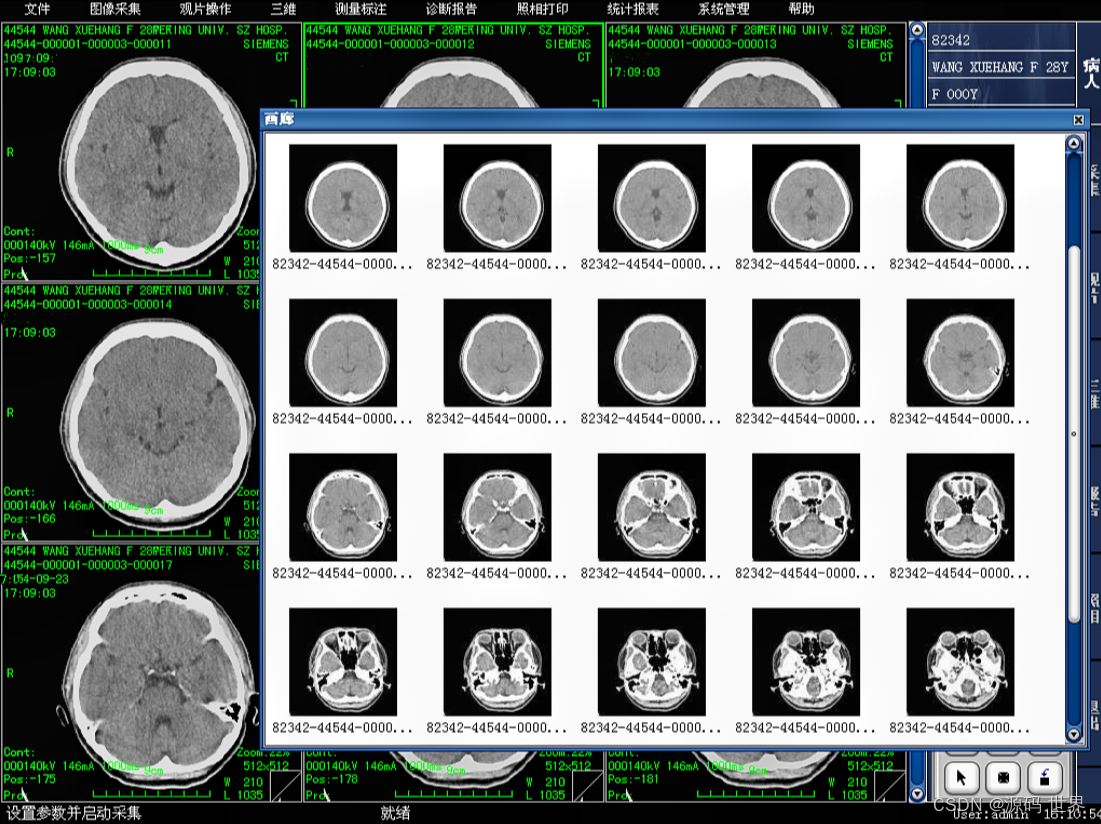

影像归档与通信系统(PACS)则专注于影像资料的存储、检索、分发和通信。PACS系统可以联接不同的影像设备(如CT、MR、XRAY、超声、核医学等),存储和管理图像,以及图像的调用与后处理。PACS系统也可以与其他系统如HIS、RIS集成,以提高工作效率和检查准确性。